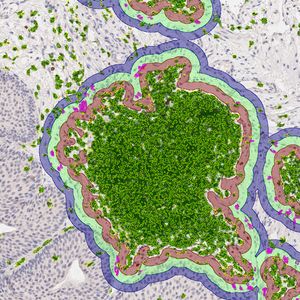

SEP 05, 2024Cell & Molecular BiologyCorynebacterium matruchotii ia a common bacterium that lives in human dental plaque; a colony is seen in this image by S ...